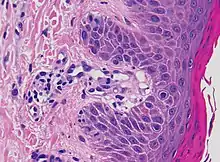

Micrograph of Schamberg disease, suggesting the spongiotic stage of a purpuric dermatitis.

Additional testing may aid diagnosis. A skin biopsy may be taken to determine capillaritis of dermal vessels.[8] Capillaritis or pigmented purpura is skin condition that has brown-reddish patches on the skin, which is caused by leaky capillaries.[9] Such skin biopsies are sent to a laboratory for a pathological examination, where each biopsy is observed under a microscope.[3] A dermatologists may also perform a dermatoscopy.[3]